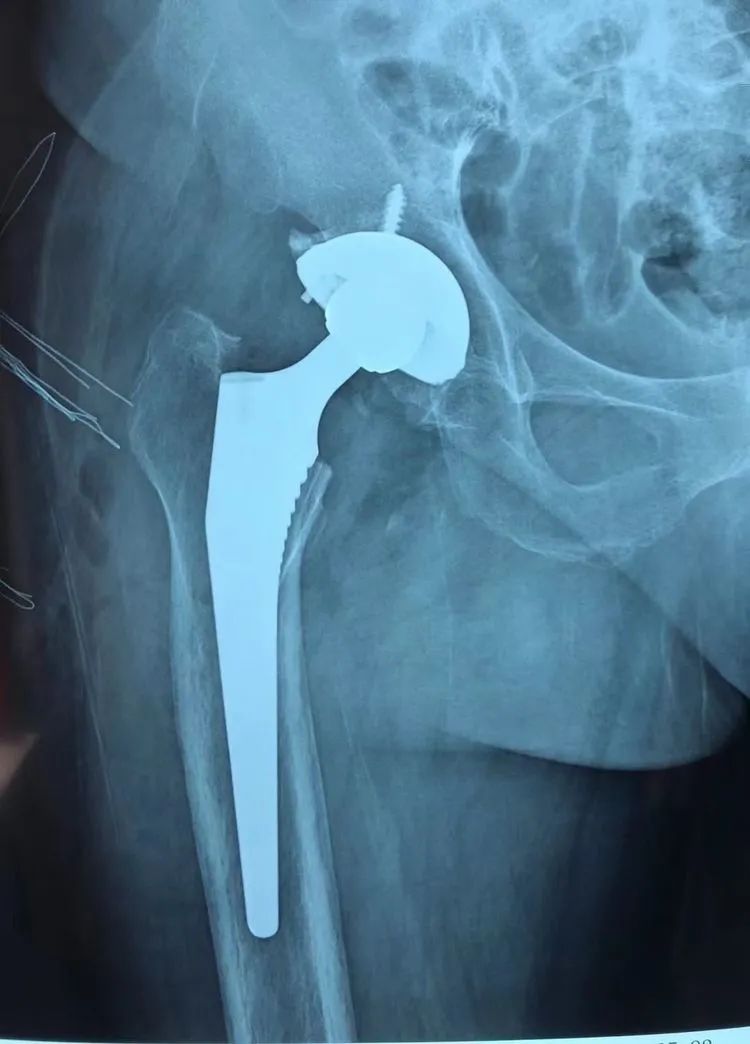

随后,在手术室团队的配合下,为其行腰硬联合麻醉下“右侧全髋关节置换术”,方成教授主刀,王怀波主任协同,熟练地切开、显露,切除、清理、安装......手术十分顺利。